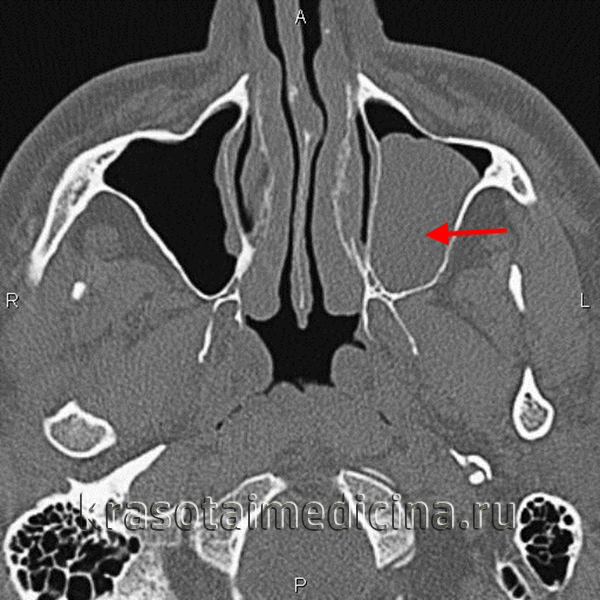

3. КТ при ювенильной ангиофиброме:

• КТ с КУ:

о Интенсивно усиливающееся мягкотканное образование возле КНО с распространением в соседние отделы носоглотки и КНЯ

о ± снижение пневматизации основной пазухи («запертое» отделяемое и опухолевый инфильтрат)

• «Костная» КТ:

о Ремоделирование костей ± деструкция

о Выбухание задней стенки верхнечелюстной пазухи кпереди

о Расширение ипсилатеральных отделов полости носа и КНЯ